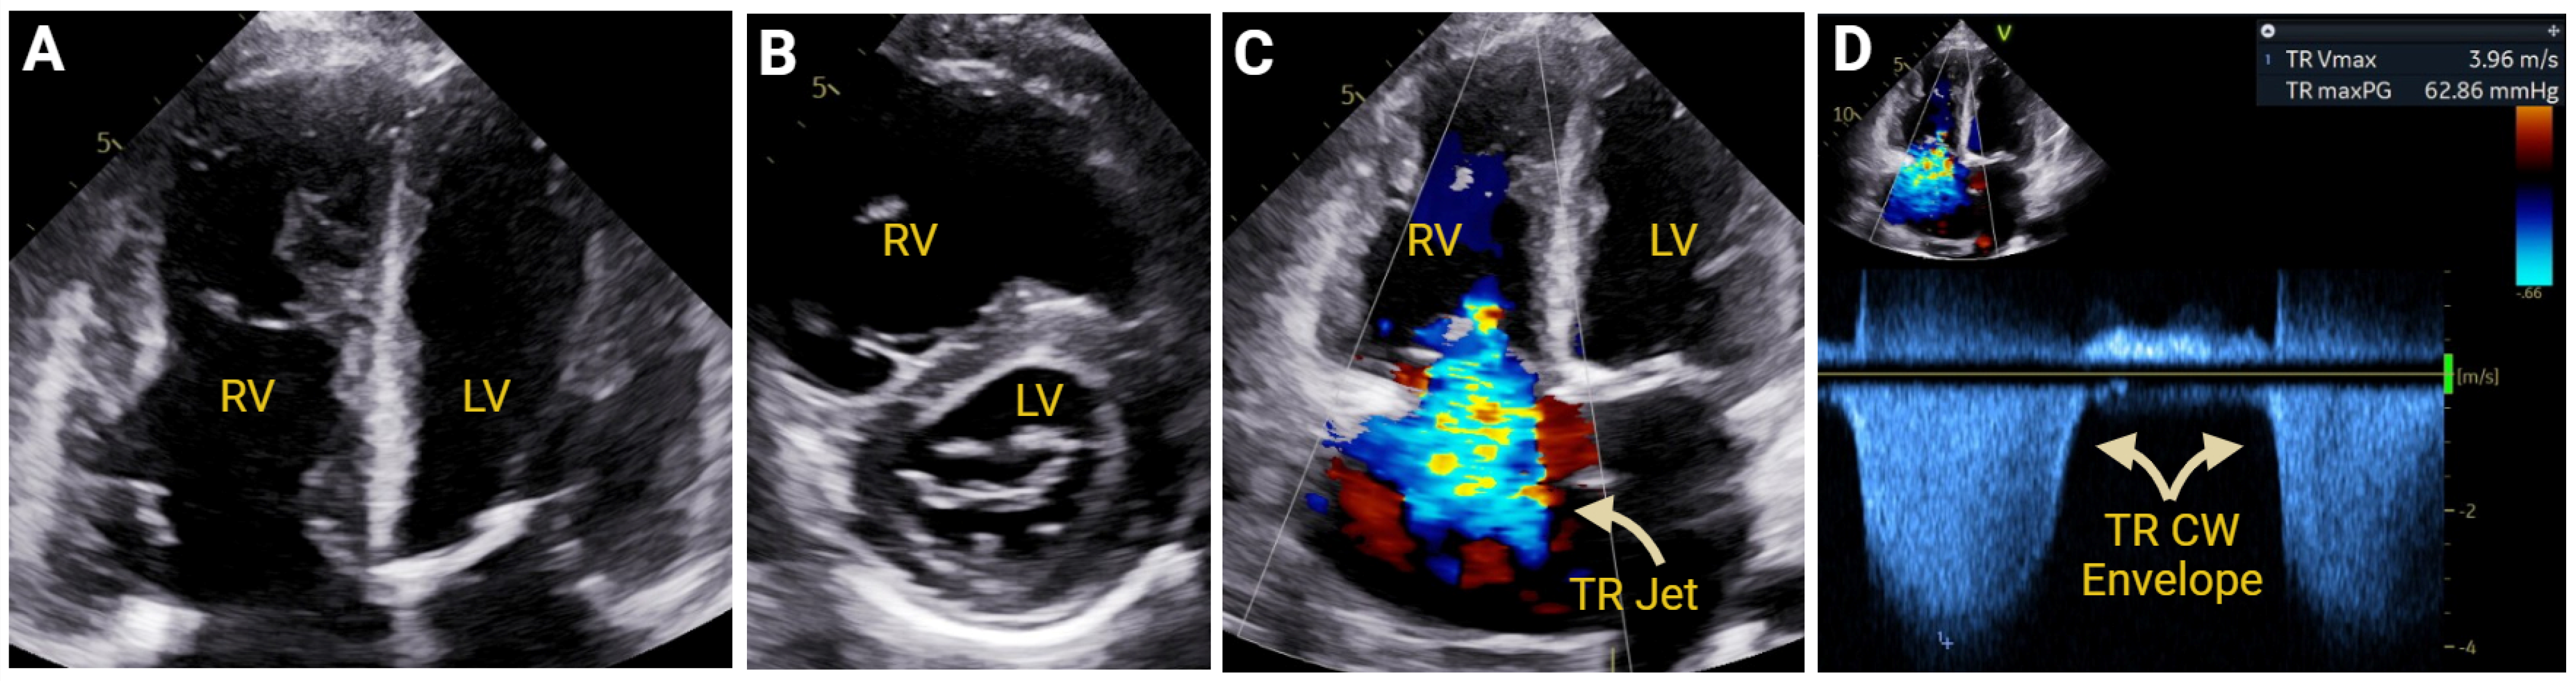

- Amsallem, M.; Sternbach, J.M.; Adigopula, S.; Kobayashi, Y.; Vu, T.A.; Zamanian, R.; Liang, D.; Dhillon, G.; Schnittger, I.; McConnell, M.V.; et al. Addressing the Controversy of Estimating Pulmonary Arterial Pressure by Echocardiography. J. Am. Soc. Echocardiogr. 2016, 29, 93–102. [Google Scholar] [CrossRef] [PubMed]

- Platts, D.G.; Vaishnav, M.; Burstow, D.J.; Craig, C.H.; Chan, J.; Sedgwick, J.L.; Scalia, G.M. Contrast microsphere enhancement of the tricuspid regurgitant spectral Doppler signal-Is it still necessary with contemporary scanners? Int. J. Cardiol. Heart Vasc. 2017, 17, 1–10. [Google Scholar] [CrossRef] [PubMed] [PubMed Central]